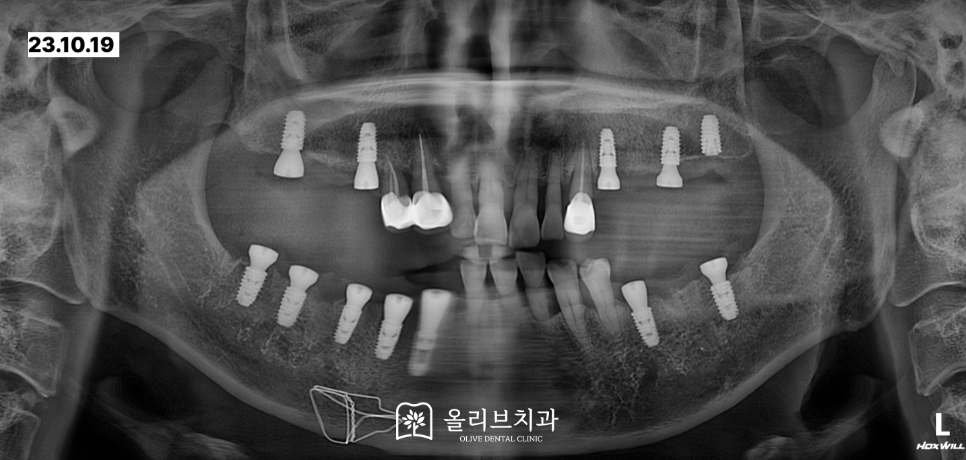

상악에 문제가 되었던 치아 2개를 발치하고 어금니부위에 어금니부위에 임플란트 5개를 식립하였습니다.

약 일주일 후 아래 7개 임플란트를 식립완료하였습니다.